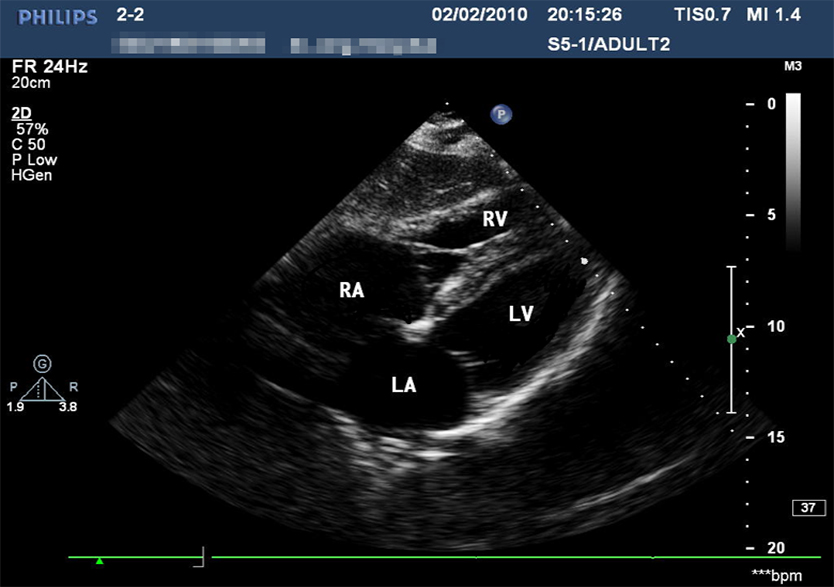

创伤超声重点评估平台2.0

产品型号 NO.TY4084